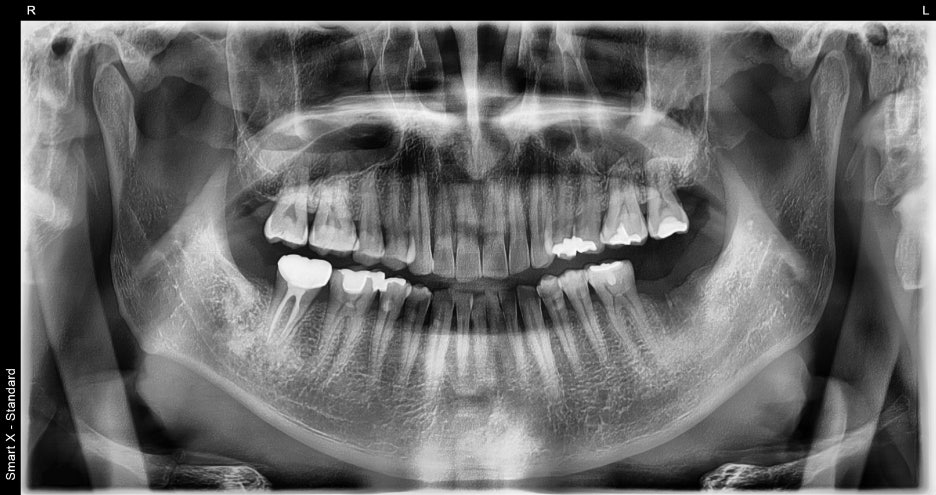

진단 결과

파노라마 엑스레이 촬영 결과,

왼쪽 아래 어금니가 이미 발치된 상태로

주변 뼈 상태는 양호하여

추가 뼈이식 없이 임플란트 식립 가능으로 확인되었습니다.

① CT 촬영 및 수술 계획 수립

– 임플란트 위치, 각도, 길이를 정밀하게 계획했습니다.

② 임플란트 식립 수술

– 국소마취 하에 왼쪽 아래 어금니 부위에

임플란트를 심었습니다.

– 뼈와 잇몸 상태가 건강하여 별도의 뼈이식은

필요하지 않았습니다.